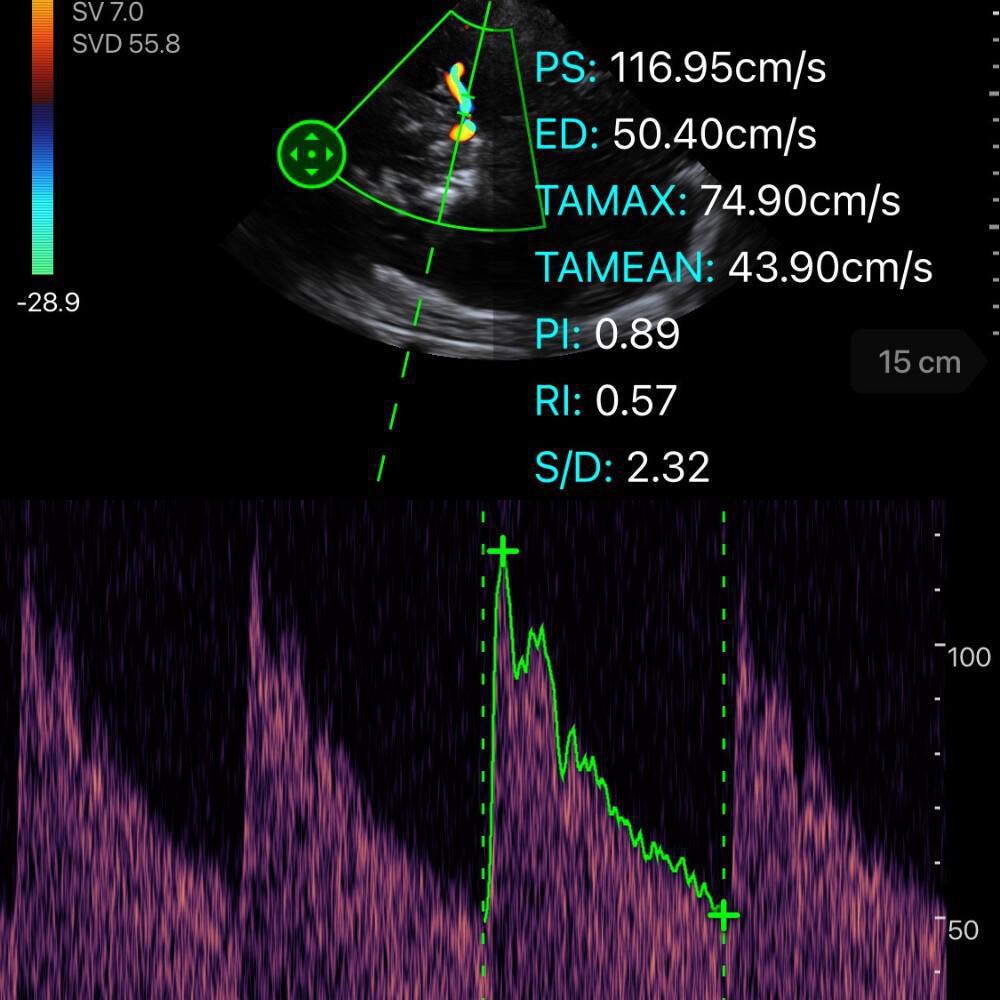

📈 Paramètres analysés

Sur le spectre Doppler :

-

VS = vitesse systolique

VD = vitesse diastolique (clé pour la PPC)

VM = vitesse moyenne

🔵 Index de pulsatilité (IP / PI)

Formule :

IP = (VS − VD) / VM

Valeur normale pratique :

IP ≤ 1

🔴 Profil hémodynamique en HTIC

Quand la PIC augmente :

VD diminue

VM diminue

IP augmente

Courbe devient très pulsatile

En phase extrême : disparition du flux diastolique

🚨 Seuils d’alerte pratiques en TCG

Profil suspect d’HTIC / hypoperfusion :

VM < 30 cm/s

VD < 20 cm/s

IP > 1,4

Profil rassurant (forte VPN pour HTIC) :

VD > 25 cm/s

IP < 1,25